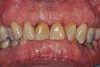

Fig 2. Pretreatment views: right lateral (Fig 2), frontal (Fig 3), and left lateral (Fig 4). Note: The maxillary right first molar (tooth No. 3) (Fig 2) would be identified as the most periodontally involved molar that was planned to be maintained.

Figure 2

Fig 3. Pretreatment views: right lateral (Fig 2), frontal (Fig 3), and left lateral (Fig 4). Note: The maxillary right first molar (tooth No. 3) (Fig 2) would be identified as the most periodontally involved molar that was planned to be maintained.

Figure 3

Fig 4. Pretreatment views: right lateral (Fig 2), frontal (Fig 3), and left lateral (Fig 4). Note: The maxillary right first molar (tooth No. 3) (Fig 2) would be identified as the most periodontally involved molar that was planned to be maintained.

Figure 4

Periodontal examination revealed generalized BOP and PDs up to 9 mm in the maxillary and mandibular molars with multiple furcations in each molar (Figure 2 through Figure 7). He presented with class I mobility in many posterior teeth and class II mobility in teeth Nos. 3 and 9 (maxillary right first molar and maxillary left central incisor, respectively). The periodontist decided to score tooth No. 3 for the PRS, as this was the most periodontally involved molar that was planned to be treated and maintained (Figure 2 and Figure 8). This tooth (maxillary right first molar = score 1) presented with probing depths of 7 mm (score 1); three total furcation invasions (score 3) (mesial [degree II furcation], buccal [degree I furcation], and distal [degree II furcation]); and a class II mobility (score 2). The total PRS for tooth No. 3 was 8, representing a "guarded" prognosis. Based on this score, the likelihood of not losing any teeth to periodontal disease for 15 years was 81%, and for 30 years the likelihood was just 56% (Figure 9).7